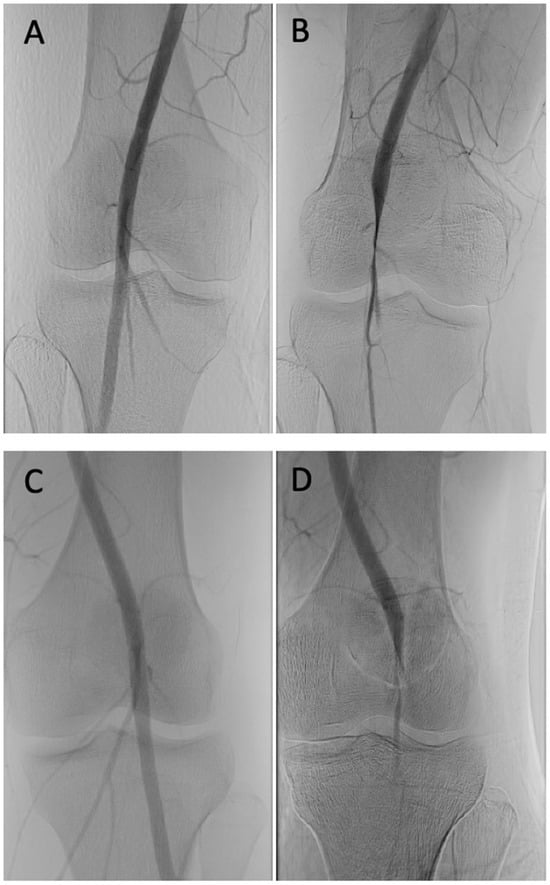

2.2. Diagnostic Testing

| Diagnosis | Compartment testing > 30 mmHg one minute after ceasing pain-provoking exercises. | CTA, MRA, or diagnostic angiography for confirmation of suspected PAES. |